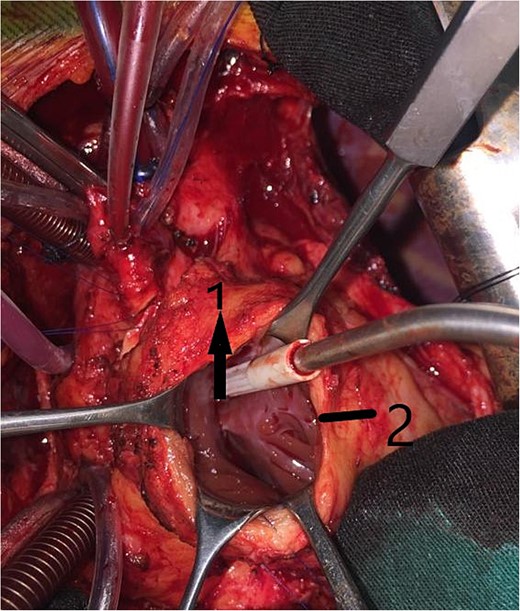

An 11-year-old girl was referred to our hospital with a main complaint of progressive exertional dyspnea. She had undergone surgical repair of SAS 6 years ago. Transthoracic echocardiogram (TTE) revealed the following findings: severe left ventricular hypertrophy, tunnel-like fibromembranous subaortic stenosis with a length of 10 mm, a peak gradient (PG) across the LVOT of 170 mmHg, and mild aortic regurgitation. Based on these findings, the patient was scheduled for elective surgical repair with a possible indication for MKO. The operation was performed via median sternotomy with great caution to avoid inadvertent rupture of any cardiac cavity due to heavy adhesions from the previous operation. The aorta was cannulated just below the takeoff of the innominate artery. Bicaval cannulation was performed to provide a bloodless field. Aortic cross-clamping was applied, and antegrade cold blood cardioplegic solution was administered via a catheter placed in the ascending aorta. The ascending aorta was opened transversely 1 cm above the sinotubular junction (Fig. 1). The aortic valve leaflets were examined carefully to confirm that the aortic valve could be preserved. LVOT was examined thoroughly, and it was clear that the stenosis in the subaortic area was so complex that simple resection through the aortic valve orifice would not be sufficient. The right ventricular outflow tract was opened transversely below the pulmonary valve. The conal papillary muscle was identified (Fig. 2). A right-angle instrument was introduced through the aortic orifice into the interventricular septum, and the tip of the instrument was used to perforate the conal septum to the left of the conal papillary muscle to prevent damage to the conduction system; the septal incision was completed with great caution to avoid damage to the aortic cusps and to extend the incision downward as necessary to completely relieve the stenotic subaortic area (Fig. 3). Interrupted 5/0 Prolene sutures were placed circumferentially around the septal incision to close the interventricular septal defect using a bovine pericardial patch to provide adequate widening of LVOT (Fig. 4). The right ventriculotomy was closed with a second bovine pericardial patch to avoid any possible obstruction of the right ventricular outflow tract (Fig. 5). The remainder of the operation was completed uneventfully. After 6 hours of mechanical ventilation, the patient was extubated, and she convalesced well postoperatively. TTE showed excellent results of the operation with PG across LVOT of 20 mmHg. On 1 year follow-up, the patient was asymptomatic and in very good general condition, and TTE findings confirmed the excellent result.

Intraoperative image showing the opened aorta. The arrow points to the aortotomy, and the star points to the stenotic left ventricular outflow tract through the aortic orifice.